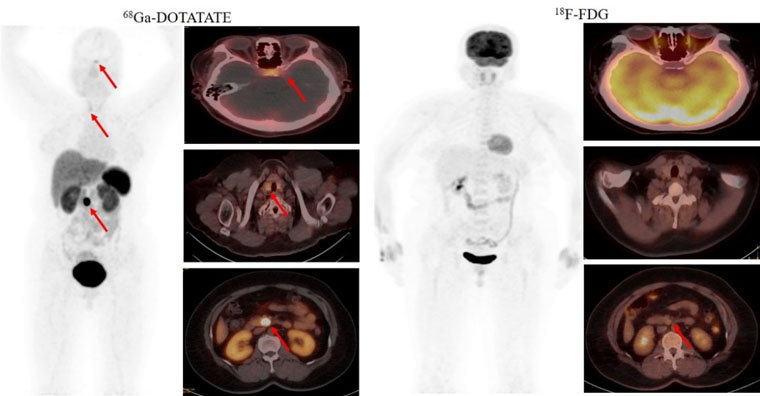

首个病例患者为一名49岁的女性,间断低血糖超过1年,甲状旁腺激素检查异常升高。脑MRI提示为脑垂体微腺瘤,上腹部MRI检查未发现明显异常。但临床怀疑胰腺存在病变,经新探针68Ga-DOTATATE PET/CT检查,发现了胰腺病灶,综合诊断多发性内分泌瘤病I型(MEN1型)。经胰腺穿刺病理证实为神经内分泌肿瘤G268Ga-DOTATATE18F-FDG PET/CT双核素的检查结果为患者临床精准诊疗提供了胰腺病灶的影像学证据。